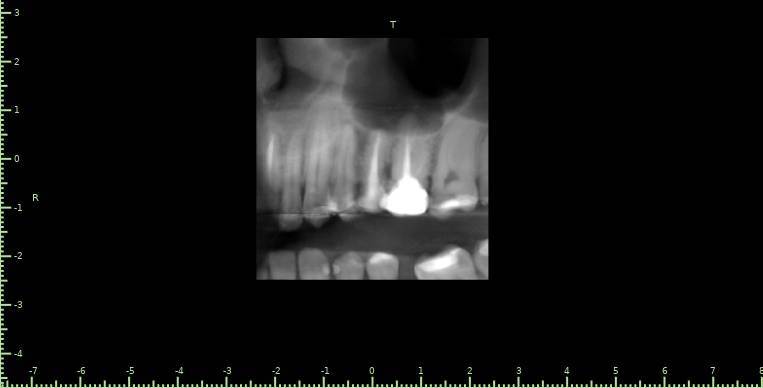

Здравствуйте, появился полгода назад свищ на десне, заполняется и лопается, затягивается и снова появляется, спустя пару месяцев обратился в стоматологию, на снимке ничего критичного не увидели, отправили домой наблюдать тип, еще прошло 3 месяца, так и не проходит и хуже не стало, болей нет никаких, только небольшая если трогать в районе свища, пойдя в другую стоматологию, сделали снимок и так же непонятно что и почему, пошел на КТ, и обратно в стоматологию, есть какая то полость, можно попробовать но нет гарантии, что пройдет, прикрепляю снимок К

ТРезультаты и плюс программа для открытия